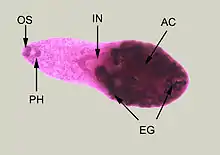

| Adult specimen stained with carmine | |

Minute teardrop-shaped flukes found in the small intestines of fish-eating birds and mammals. The eggs are hard to tell apart from other related species so there is no accurate estimate of human infection. H. heterophyes is a small trematode, ranging up to 1.4mm long and 0.5mm wide.[4] It is covered with scale-like spikes and those spikes can range from 50–62.[9] Their pharynx is completely developed and connected to the cecum of the small intestines. Their sucker (mouth) is covered with spikes and its covering the genital opening. This means, they share one hole for eating and reproduction. Their testes is located at the posterior of the parasite and the testes are side by side.[4] The ovaries are located in the medial of the parasite, right above the testes.[4] The ventral sucker also known as the acetabulum is located at the ventral of the parasite.[4] The ventral sucker helps them attach to the host. Morphology can change depending on what fish it lives on.